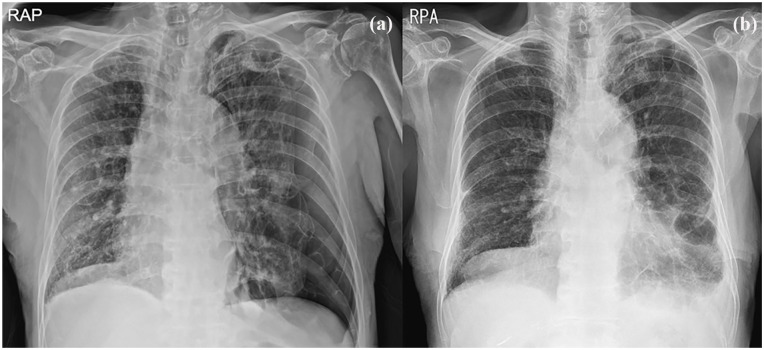

我报告2例老年继发性自发性气胸患者用50%葡萄糖水(DW)进行胸膜融合术。在这两个病例中,胸部计算机断层扫描显示大气胸伴肺气肿和多个大泡。考虑到患者的年龄和潜在的肺部疾病,预计他们不会忍受手术治疗。以前,胸膜固定术是使用其他化学药剂进行的。然而,化学性胸膜穿透术可伴有胸痛、发热,很少伴有呼吸衰竭。2例胸膜截留术,胸膜截留率50%,气胸消退,无并发症。我建议即使是不能耐受手术或化学胸膜固定术的老年患者,也可以考虑使用50% DW胸膜固定术,因为它相对更安全有效。

I report 2 cases of pleurodesis with 50% dextrose water (DW) in very elderly patients with secondary spontaneous pneumothorax. In both cases, a chest computed tomography scan showed a large pneumothorax with emphysema and multiple bullae. Patients were expected not to tolerate surgical treatment, considering their old age and underlying pulmonary disease. Previously, pleurodesis is performed using other chemical agents. However, chemical pleurodesis can be associated with chest pain, fever, and rarely, respiratory failure. Pleurodesis with 50% DW was performed in 2 patients with resolution of pneumothorax without complications. I recommend that even in elderly patients who could not tolerate surgery or chemical pleurodesis, pleurodesis using 50% DW could be considered because it is relatively safer and effective.